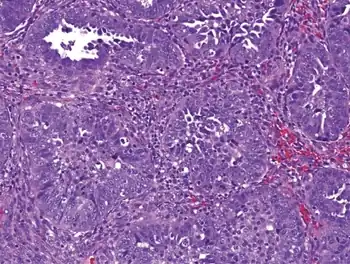

| Opsoclonus as suspected paraneoplastic syndrome of endometrial cancer | |